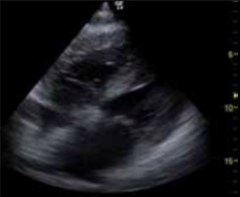

Really thick RV wall in a patient with asthma

Poorly controlled asthma can cause pulmonary HTN and increased RV wall thickness

How do confirm that you are in the RV

Moderator band